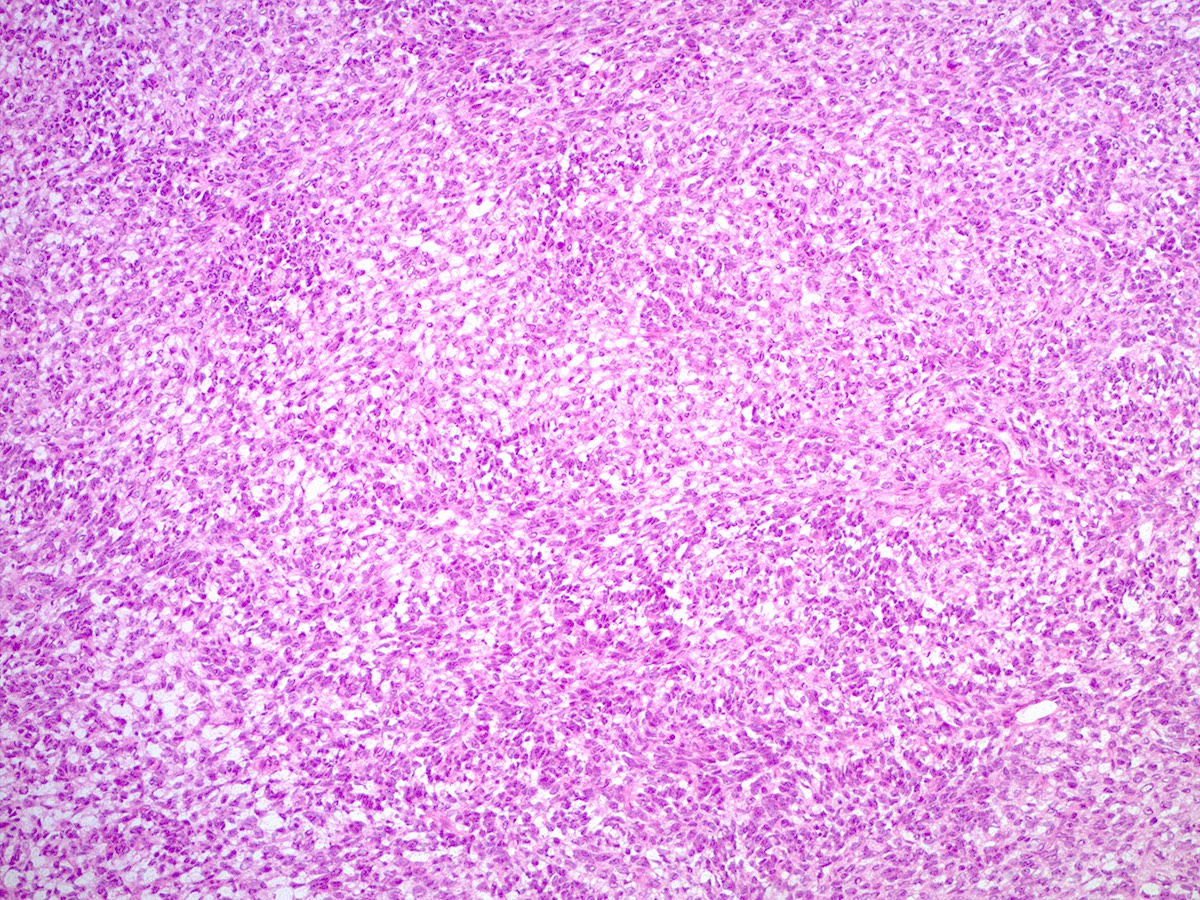

Microscopic (histologic) description

- Difficulty of histologic diagnosis increases with tumor grade

- Poorly differentiated

- Diffuse sheets of immature, sarcomatoid Sertoli cells with moderate to marked nuclear atypia and only rare foci of vague cord formation

- Increased mitotic activity, up to 20 mitoses per 10 high power fields

- Leydig cells are difficult to find; a few small clusters are typically located at the periphery of tumor nodules